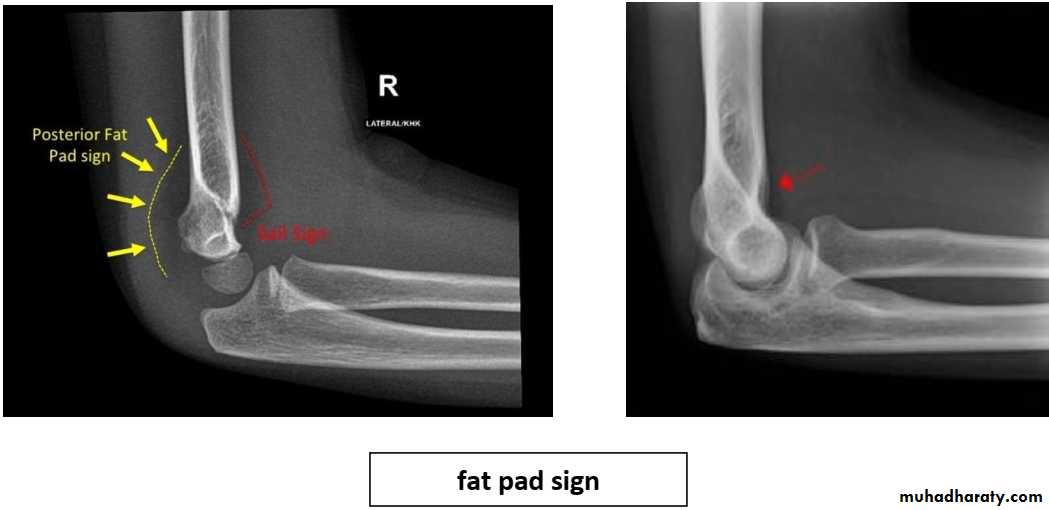

Fat pad sign/sail sign : A non-displaced fracture can be difficult to identify and a fracture line may not be visible on the X-rays. However, the presence of a joint effusion is helpful in identifying a non-displaced fracture. Bleeding from the fracture expands the joint capsule and is visualized on the lateral view as a darker area anteriorly and posteriorly, and is known as the sail sign.